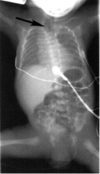

What is this?

Pyloric stenosis

Also look for

string sign, double tract sign, shoulder sign